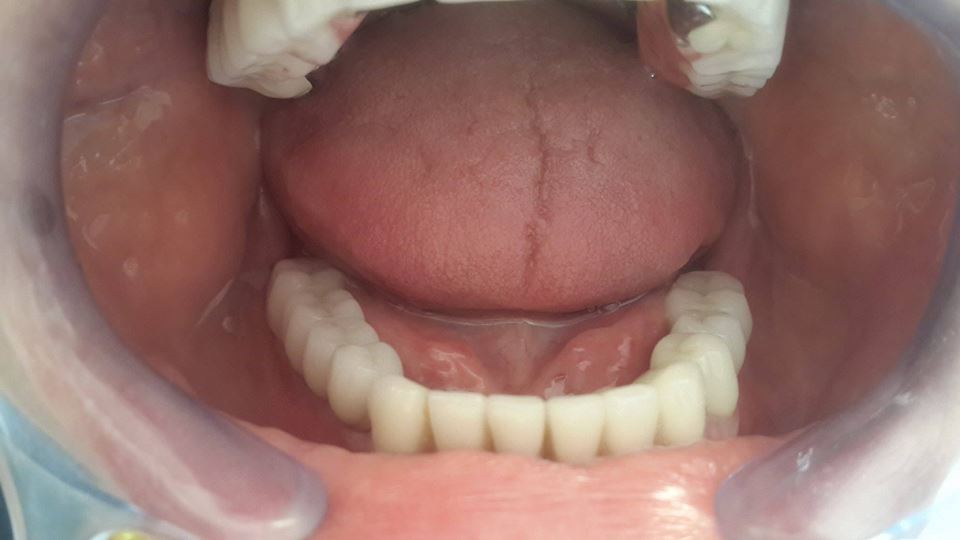

An example of complete rehabilitation of the oral cavity. Treatment included the removal of the old prosthesis, treatment of paradontitis, removal of a large cyst, implantation, clasp prosthesis.